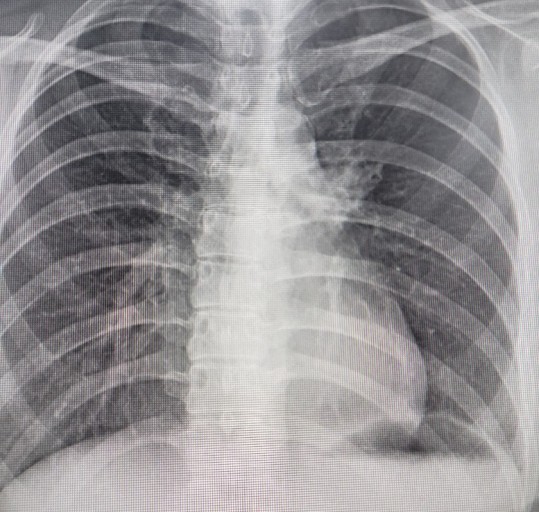

폐렴 증상 폐렴은 폐의 세균, 바이러스, 곰팡이 등 감염으로 인해

폐포(폐 속의 공기 주머니)에 염증이 생기고, 고름이나 액체가 차는 질환입니다.

이로 인해 산소 교환이 원활하지 못해 호흡곤란, 기침, 발열 등이 나타나죠.특히 영유아, 고령층, 면역력이 약한 사람에게서 더 위험하며